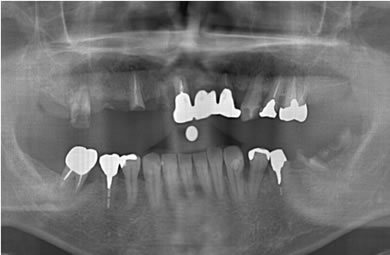

| 性別/年齢 | 男性 / 44歳 | ||||||||||||||||||||||||||||||||

| 主訴 | 前歯がぐらついている。 | ||||||||||||||||||||||||||||||||

| 治療方針 | 骨再生療法にて上顎の骨を増やしインプラント治療にて審美的・機能的回復を行う。 | ||||||||||||||||||||||||||||||||

| 治療内容 | インプラント7本(ソケットリフト)、ハイブリッドセラミック12本 | ||||||||||||||||||||||||||||||||

| 総治療費 | 3,207,924円 | ||||||||||||||||||||||||||||||||

| 治療期間 | 1年6ヶ月 |